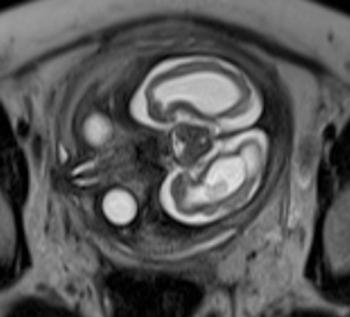

In a third study, ultrasound and fetal MRI were performed on pregnant patients with Zika virus infection at different gestational ages. Once the babies were born, they underwent ultrasound, CT and MRI. The researchers then created 3-D virtual and physical models of the skulls. More than half the babies had microcephaly, brain calcifications and loss of brain tissue volume, along with other structural changes.

"The emergence of Zika virus in the Americas has coincided with increased reports of babies born with microcephaly," said study author Heron Werner Jr., M.D., Ph.D., from the Department of Radiology at Clínica de Diagnóstico por Imagem. "An early diagnosis may help in treating these babies after birth. Moreover, the knowledge of abnormalities present in the central nervous system may give hints about the pathophysiology of the disease."